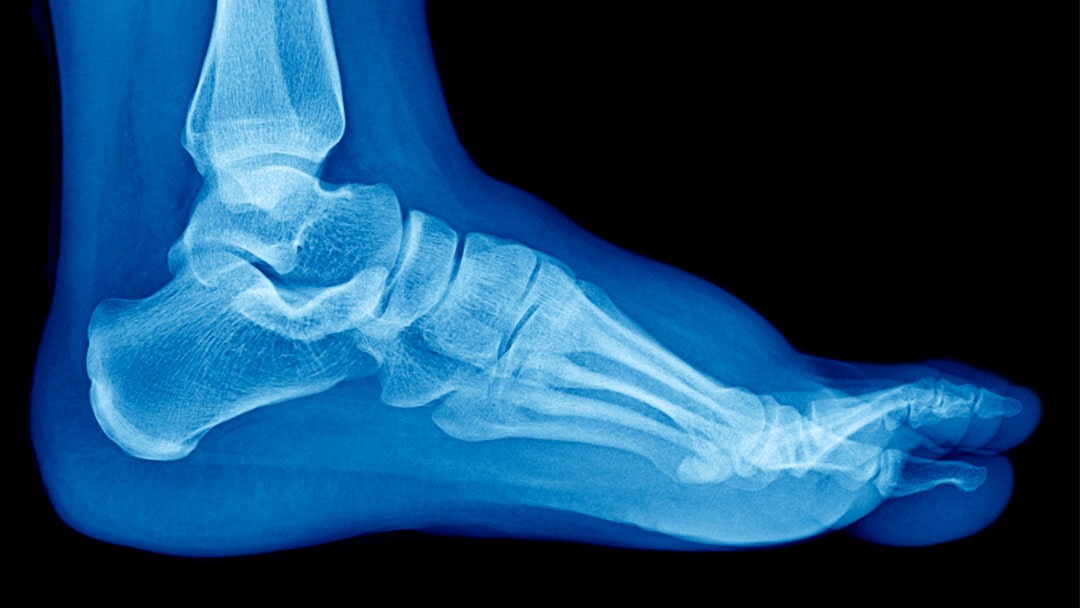

Along the inside of the foot is a raised area called the medial longitudinal arch. In flatfoot, this arch is lower than normal—or completely flattened—often accompanied by heel valgus, where the upper heel tilts inward relative to the lower leg.

- Flatfoot happens when the talus bone “collapses” downward, the heel tilts inward, and the posterior tibial tendon is stretched trying to support the arch.

Diagnosis usually requires only a physical exam. X-rays or other imaging tests are performed if the pain is significant.